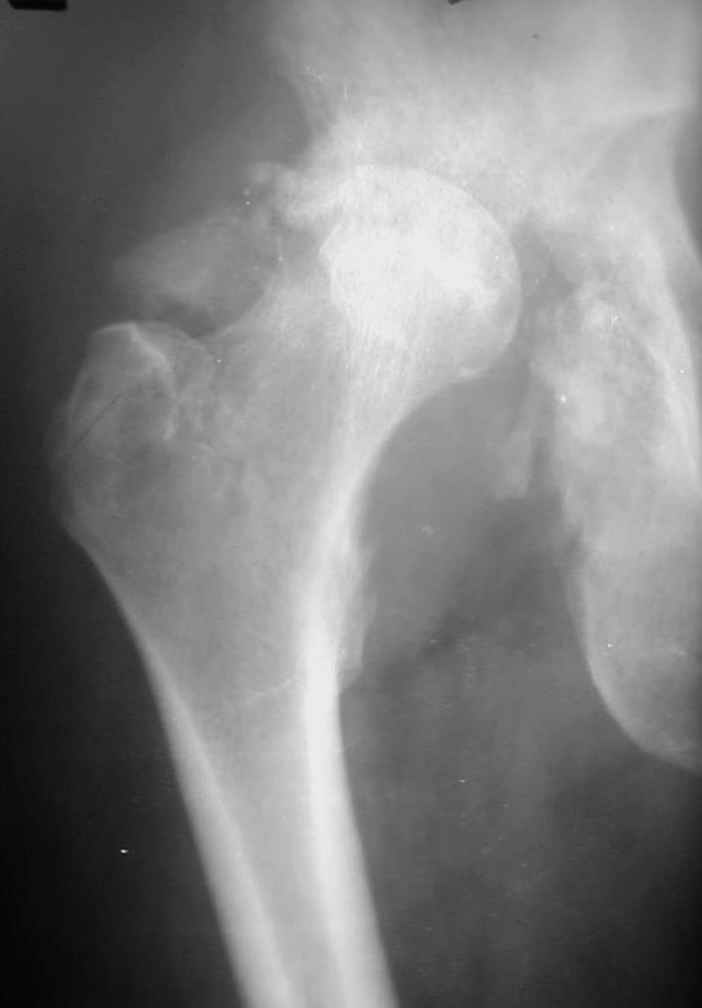

Уважаемые коллеги! На консультацию пришел молодой человек 23 лет с застарелым задним вывихомбедра. После травмы прошло 2,5 ГОДА.

Были переломы бедра и голени на этой же стороне, которые благополучно срослись после остеосинтеза. вывих бедра был пропущен. В настоящее время ходит без дополнительной опоры, есстественно, сильно хромает, выражен болевой синдром, парез седалищного нерва. Сформировался неоартроз в подвздошной области, виден неправильно сросшийся перелом задней колонны, сгибание в суставе до 80.

Что делать? Честно говоря, на таких сроках опыта лечения подобных больных нет (мах 8 мес). Постепенно низводить аппаратом и затем ставить эндопротез там где должен быть сустав? Или ставить протез выше истинной впадины с укорочением конечности, а затем удлиннять бедро или голень? У кого есть подобный опыт, подскажите?